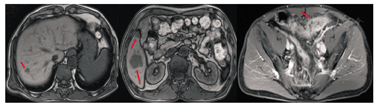

男性患者,56岁,因"排粪习惯改变1月余,肛门坠胀2周余" 。于2015年4月23日入院。患者于2015年3月出现粪便变细,排粪习惯改变,此后伴有肛门坠胀感及间歇性下腹部隐痛。入院查体:一般状况可,全身浅表淋巴结未触及,心肺未见明显异常,左下腹轻微压痛,无反跳痛,肝脾肋下未触及,肾脏未触及,肝区无叩击痛。美国东部肿瘤协作组(ECOG)评分:1分。辅助检查(2015年4月):电子全结肠镜提示:距肛30~40 cm可见溃疡性新生物,累及肠腔全周,导致管腔狭窄,活检质脆,易出血。病理活检提示为腺癌;腹部增强CT提示:结肠癌可能性,周围脂肪间隙内可见增大淋巴结,伴肝脏多发占位,考虑转移癌。胸部平扫CT未见明显异常。全腹部MRI提示:乙状结肠肠壁信号不均匀增高,肠壁不均匀增厚,增强可见强化,管腔狭窄,该段肠管浆膜层稍毛糙;肝实质内多发长T1、长T2信号影,增强可见环形强化,最大者位于肝右叶,见图1。肿瘤标志物:癌胚抗原(CEA)为55.41 μg/L,血清糖类抗原(CA)19-9<0.60 U/ml,CA72-4为1.09 U/ml。诊断为乙状结肠腺癌伴肝脏多发转移(cT4aN+M1a,Ⅳ期)。该病例由四川大学华西医院结直肠癌MDT协作组提供。

影像科:患者肿瘤位于乙状结肠,肿瘤侵及浆膜层,致使肠管浆膜层稍毛糙(T4),周围脂肪间隙内可见增大的淋巴结,多考虑转移(N+)。肝脏内可见多发的占位结节,最大者位于右肝(2.7 cm),考虑肝多发转移(M1a),其余强化结节为血管瘤。